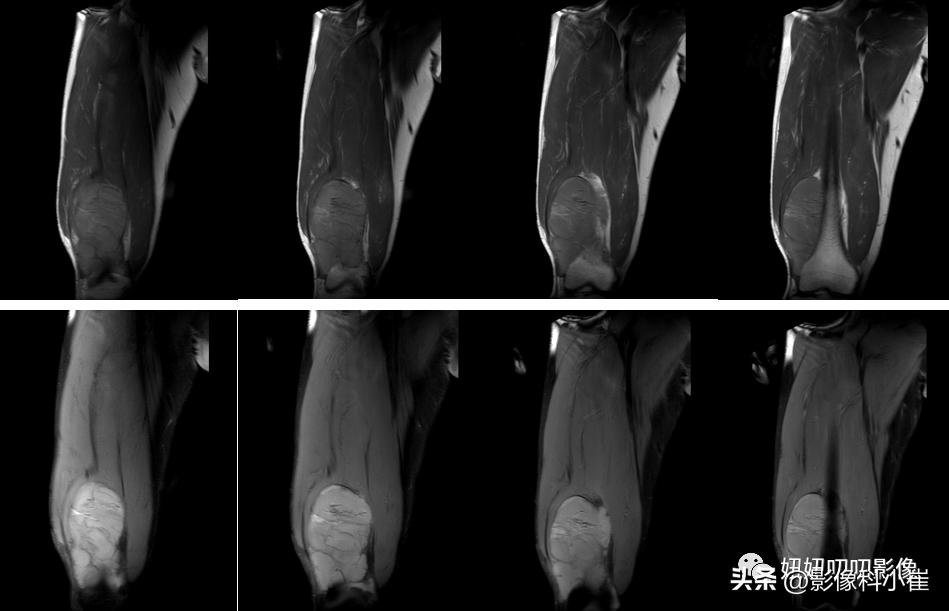

影像描述:

左侧股骨后内侧见卵圆形稍短T1 长T2 信号灶,边界清晰,大小约6.7cmX6.4cm X13.2cm,压脂序列信号强度未见明显减低。内见多发细线状长T1短 T2 信号。DWI 未见明显弥散受限。周围软组织未见明显异常信号灶。

粘液,一看就看到了,T1亮的,压脂低了,有脂肪,完了,结束,粘液脂肪肉瘤。